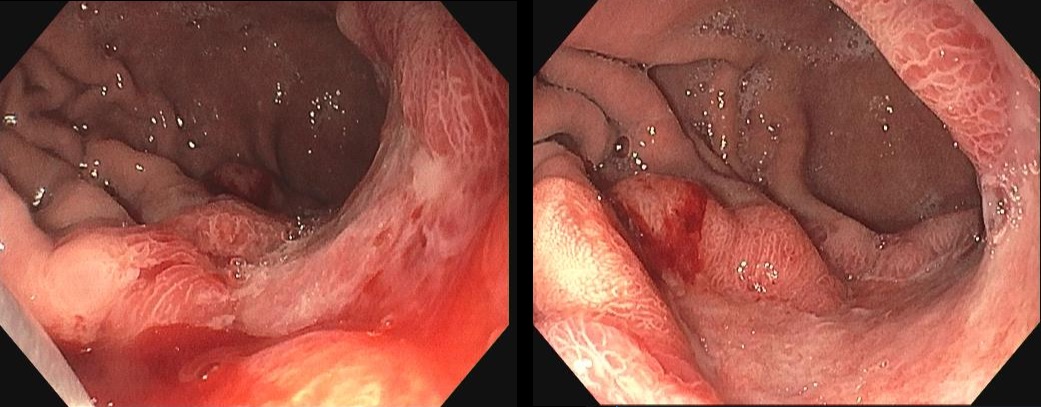

Case presentation: A 39-year-old man was initially diagnosed with lung cancer based on computed tomography and histopathologic findings. He was treated with 2 lines of chemotherapy over an 8-month period, the neoplastic lung lesions progressed, and he was referred to palliative care. Two years after his initial diagnosis, during the management of an actively bleeding gastric tumor, he was diagnosed with HIV and referred to an infectious disease unit. Immediate antiretroviral treatment was initiated after diagnosis, and further evaluation confirmed the presence of B-cell lymphoma. A retrospective review suggested that the initial cancer diagnosis was likely misinterpreted and was in fact lymphoma, a malignancy commonly associated with HIV. Lymphoma treatment was initiated, and after 1 year, the patient achieved HIV-1 virologic suppression and near-complete remission of all lesions.